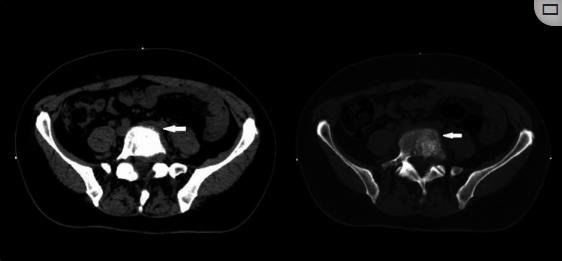

图2、腰椎CT扫描,轴面

腰椎CT显示病变涉及身体,左椎弓根和L5椎骨的左上关节面